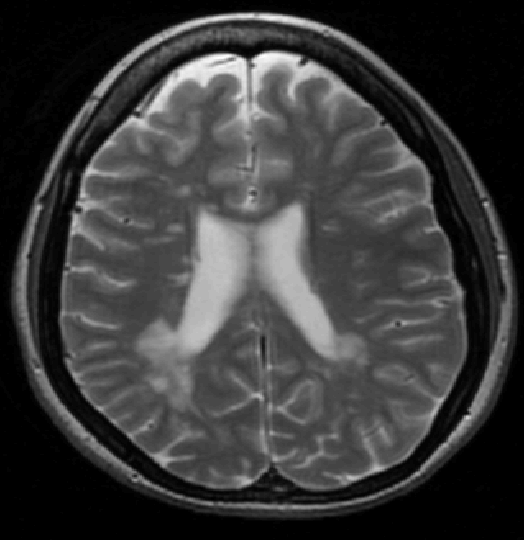

We use images from three different studies (see Fig. 1 for examples of slices):

10 MS patients from the MS Lesion Challenge [11] scanned at the Children’s Hospital of Boston (CHB), scanned with T1, T2 and FLAIR at 0.50.50.5mm resolution.

10 MS patients from the MS Lesion Challenge [11] scanned at the University of North Carolina (UNC), scanned with T1, T2 and FLAIR at 0.50.50.5mm resolution.

- 3.

Here again the differences between study populations influence the class priors. On average, the percentage of voxels that are lesions are 1.6%, 2.6% and 0.2% in CHB, RSS and UNC respectively. The differences between subjects also vary: these are relatively small for CHB and UNC, but very large for RSS. In RSS, the subject with the least lesion voxels has only 0.08%, while the patient with the most lesion voxels has 14.3%.